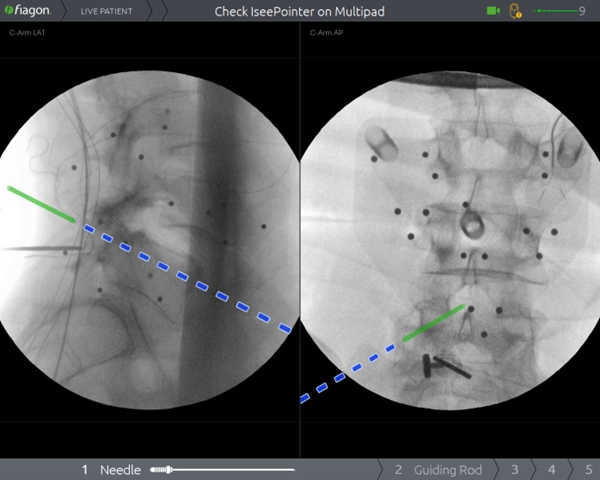

过去,受限于技术和设备,在脊柱上做手术,犹如在“暗箱”内操作,需要反复进行X线透视来判断术中状况,手术时间长,神经、血管损伤风险大。脊柱手术通常需要置入多枚螺钉,在没有先进设备辅助的情况下,医生只能凭经验操作,增加了相应的手术风险。脊柱手术的精准性和安全性一直是医生和患者最为关注的问题。而Joimax电磁导航系统作为目前世界最知名的导航系统,无传统光学导航系统“红外线遮挡”问题,并且不占用手术空间、可弯曲器械能实现尖端导航、定位器小巧,能实现多节段同步导航。骨二科(脊柱外科)李浩鹏主任表示,将导航系统应用于脊柱手术中,可以为医生呈现实时、直观的三维影像导航信息,帮助医生准确规划和及时更新手术方案,提高置钉的准确性,降低误伤神经、血管的风险,有效减少手术并发症,缩短住院时间,帮助患者及早恢复日常生活。

2020年1月9日,骨二科(脊柱外科)王栋教授团队成功将电磁导航技术引入到脊柱手术中,开展了医院首例电磁导航腰椎后方椎间融合术(PLIF)和首例电磁导航经皮穿刺椎体成形术(PVP)。手术当日,通过简单的安装信号发射器、定位仪并进行2D影像认证后,王栋教授团队在导航的辅助下,轻松完成原先脊柱手术中风险巨大的椎体植钉过程,随后的椎管减压及水泥注入等步骤一气呵成,有效缩短了手术时间、术中投射次数,大大降低了手术风险。